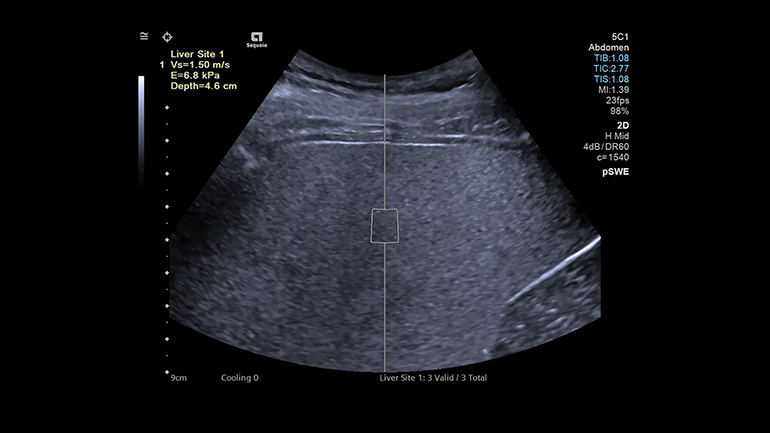

Технология pSWE

Уверенность в точности измерений, проведенных в режиме эластографии, обеспечивается полным отчетом по оценке состояния исследуемой ткани, включая рекомендованный показатель контроля качества — отношение межквартильного диапазона (IQR) к медиане полученных данных.